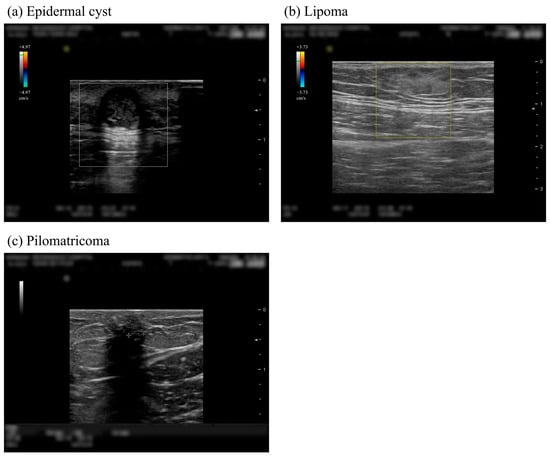

:1. Introduction

2.2. Data Preprocessing